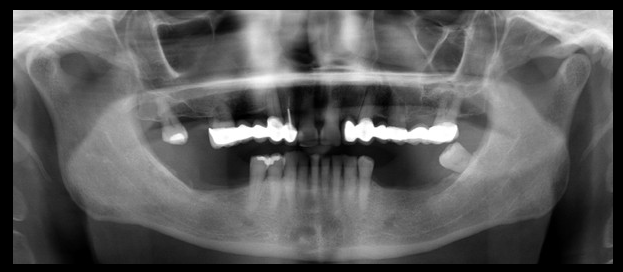

Paciente femenino de 54 años de edad, asintomática, es referida a la consulta para la evaluación con Tomografía volumétrica previa a la colocación de implantes. A la observación de los cortes axiales se evidencian dos raíces en la pieza 3.3, el corte transaxial muestra la bifurcación a nivel del tercio cervical.